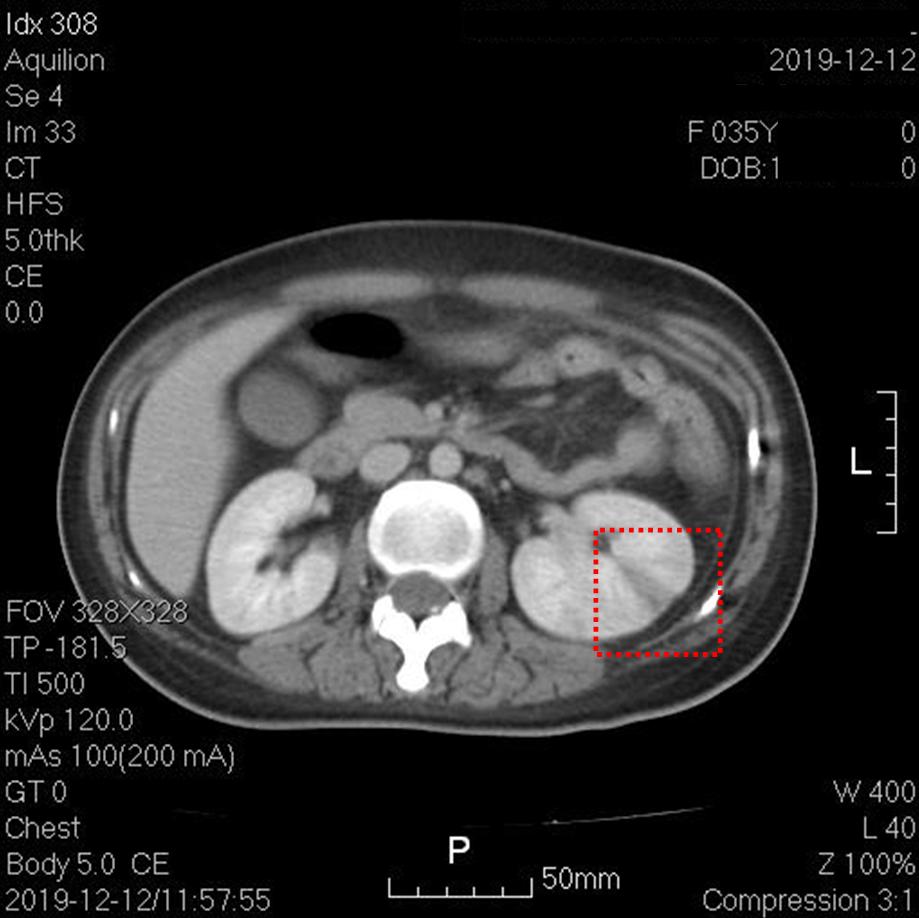

上图红框内为脾梗死。其他层面脾脏还可见数个楔形低密度灶。

上图红框内为左肾梗死。其他层面右肾也可见楔形低密度灶。